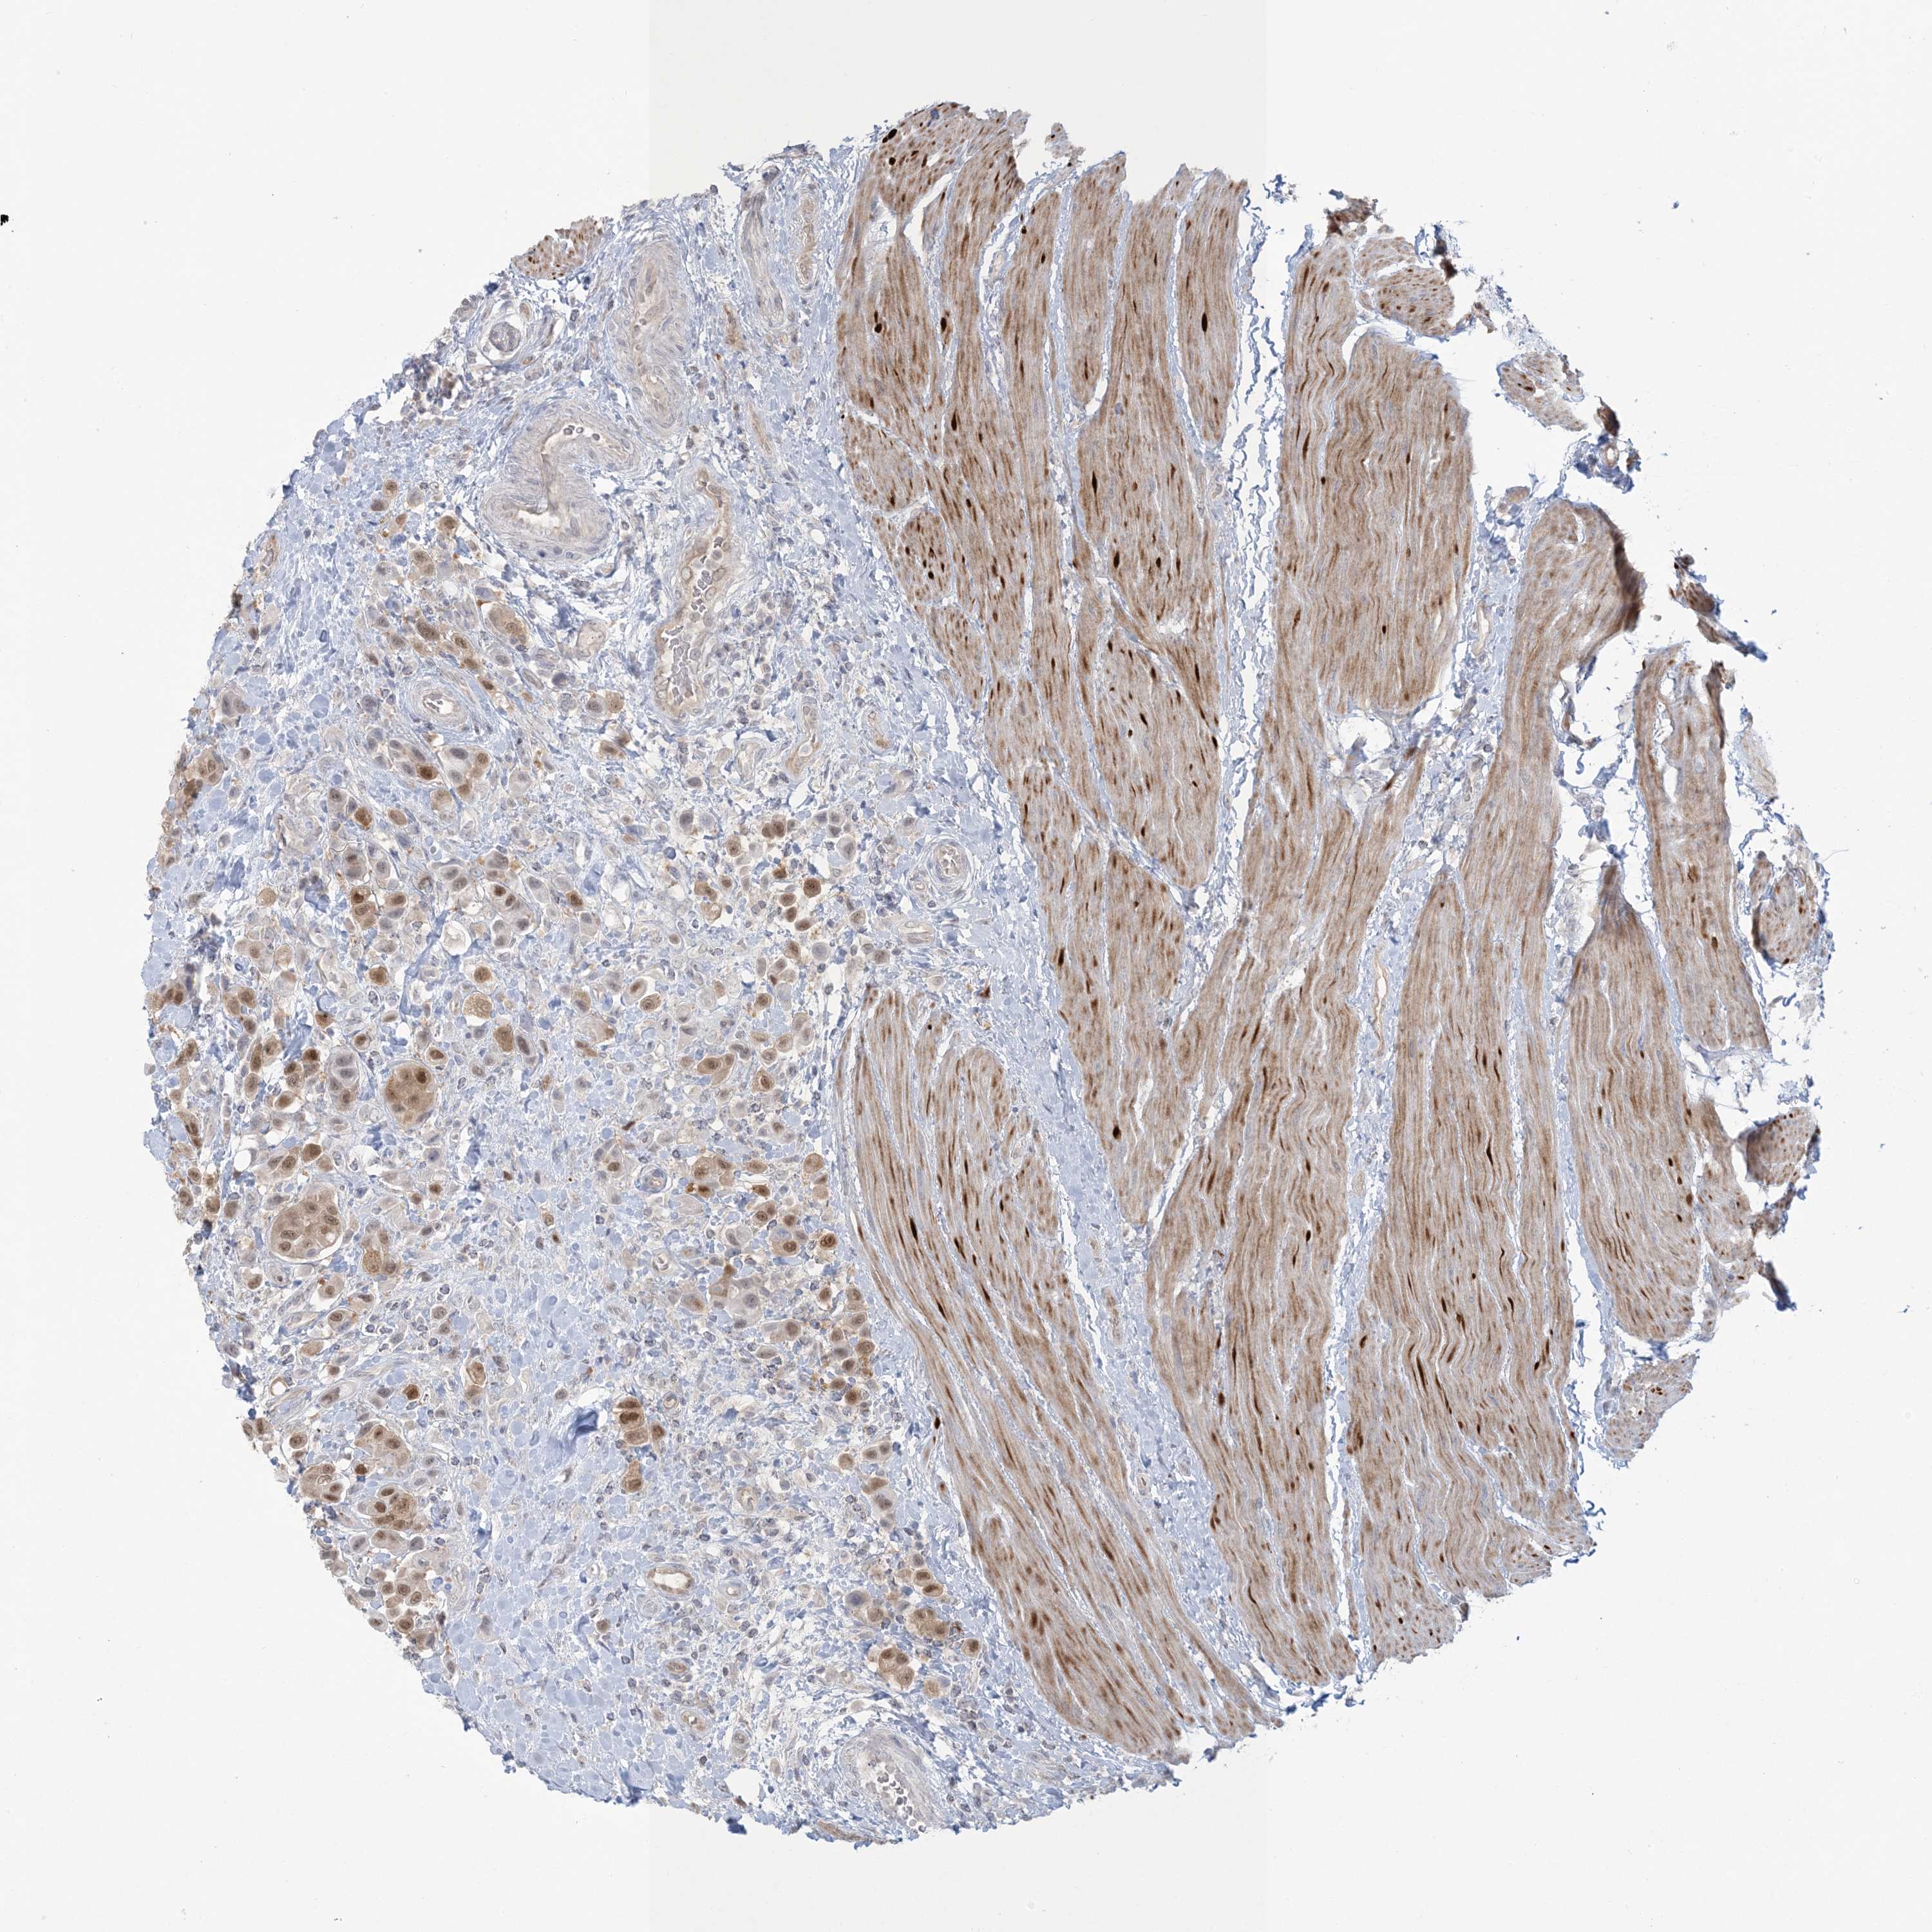

UROTHELIAL CANCER - Protein expressioni

A mouse-over function shows sample information and annotation data. Click on an image to view it in a full screen mode. Samples can be filtered based on level of antibody staining by selecting one or several of the following categories: high, medium, low and not detected. The assay and annotation is described here.

Note that samples used for immunohistochemistry by the Human Protein Atlas do not correspond to samples in the TCGA dataset.

Antibody stainingi

Antibody staining in the annotated cell types in the current human tissue is reported as not detected, low, medium, or high, based on conventional immunohistochemistry profiling in selected tissues. This score is based on the combination of the staining intensity and fraction of stained cells.

Each image is clickable and will lead to virtual microscopy that enables deeper exploration of all samples and also displays staining intensity scores, fraction scores and subcellular localization as well as patient and tissue information for each sample.

Antibody HPA029052

Antibody CAB020944

Urothelial carcinoma, High grade

Urothelial carcinoma, Low grade